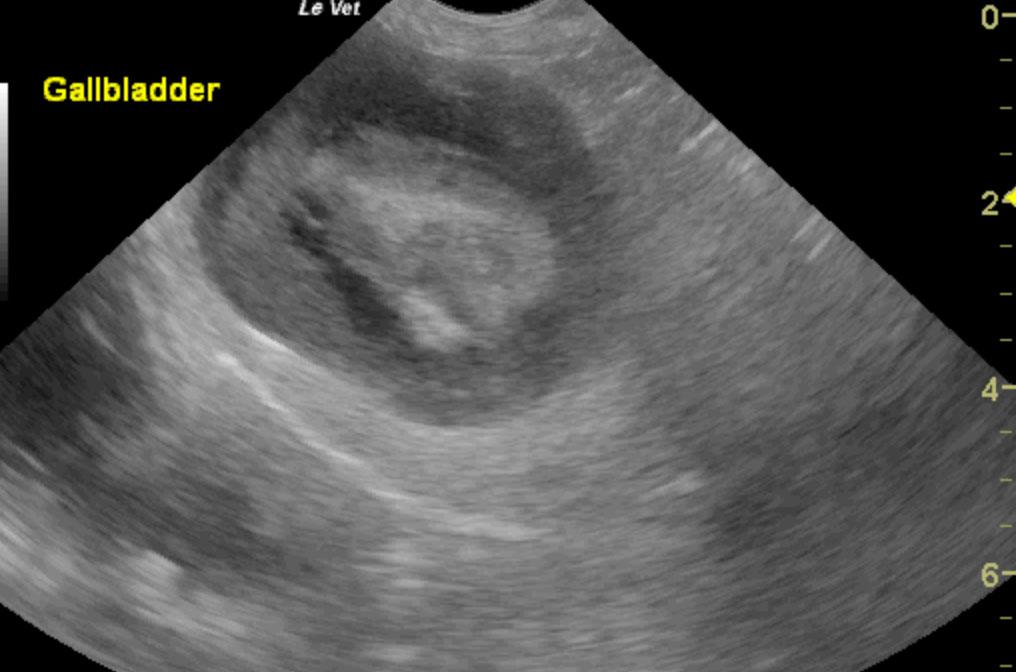

Increased echogenic appearance of the liver. Full gall bladder containing hyperechoic sludge-like material. Bile duct not visualized.

The most likely etiology for the gall bladder pathology would be a mucocele with cholicystitis another possibility. This would explain the progressive elevation of ALP activity with normalization of ALT, bilirubin, and albumin. As there is a weak association between mucocele and Cushing’s disease, screening for Cushing’s disease may be indicated if there are supporting clinical signs. Recommended therapy is surgery (cholecystectomy, cholecystotomy, cholecysto-enterostomy) as non-surgical resolution has only been reported in a hand-full of cases. Non-surgical management would include liver diet, antibiotics (penicillin, cephalosporin), and anti-emetics.

The patient was euthanized on the table during surgery. There were already a lot of adhesions around the liver and gallbladder, and the very distended gallbladder ruptured spectacularly right at the junction of the cystic duct while trying to free the adhesions. The cystic duct was also completely occluded.